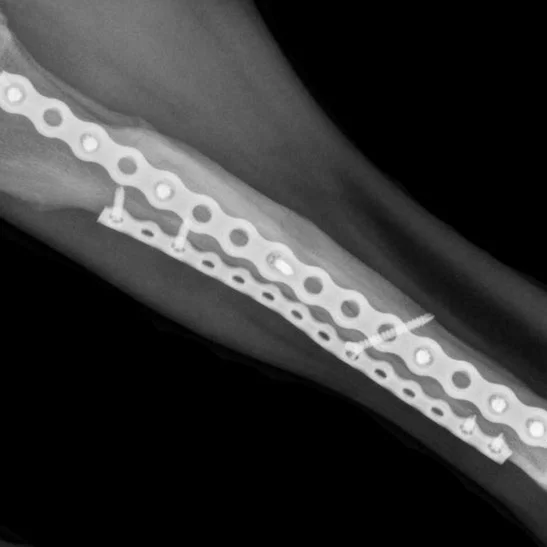

KYON ALPS-II Fracture Plating

ALPS-II plates are multipurpose Advanced Locking Plate System (ALPS) plates used for bone plating. They are second-generation locking plates based on ALPS® Technology and are an integral part of the ALPS® Product Range.

ALPS-II plates are designed to meet the needs of veterinary professionals:

Shape it. With ALPS-II, contouring in three dimensions with one single tool makes simple repairs ideal and complex repairs possible.

Anchor the way you want it. Monocortical and bicortical locking, compression or angulated KLS™ with beads and fixed-angle anchoring – everything is possible.

Faster and easier to use. Anchoring by KLS™ is easy, fast and safe.

• ALPS-II is a standard plate available in a wide range of sizes ideal for simple repairs and complex repairs requiring extensive contouring.

• ALPS-IIS is an extra strong plate available in a wide range of sizes ideal for repairs requiring extra strength or where double plating is not feasible.